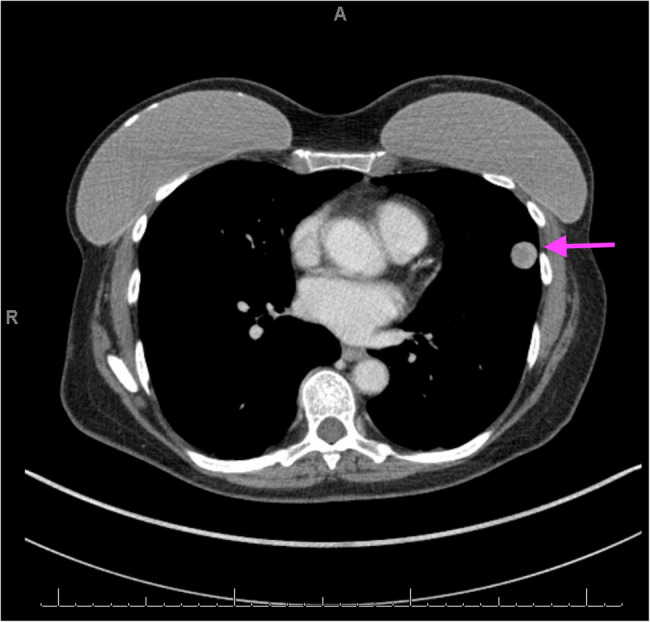

Results: A senior lady with a remote history of an unknown uterine neoplasm. Imaging of the chest revealed bilateral, enlarging pulmonary nodules, which were histologically and immunohistochemically characterized as mesenchymal-like neoplastic cells with sex cord and neuroendocrine differentiation. RNA-based next-generation sequencing identified a complex JAZF1::DLG5::PHF1 fusion, confirming a diagnosis of metastatic endometrial stromal sarcoma with sex cord and neuroendocrine differentiation.